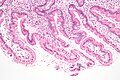

Giardiasis. H&E stain. | |

| LM | flagellate protozoa - pale/transluence on H&E, 12-15 micrometers (long axis) x 6-10 micrometers (short axis); +/-loss of villi, intraepithelial lymphocytes, inflammatory cells - especially close to the luminal surface |

- +/-Loss of villi.

- Intraepithelial lymphocytes.

- +Other inflammatory cells, especially PMNs, close to the luminal surface.

- Flagellate protozoa -- diagnostic feature.

- Organisms often at site of bad inflammation.

- Pale/translucent on H&E.

- Size: 12-15 micrometers (long axis) x 6-10 micrometers (short axis) -- if seen completely.[3]

- Often look like a crescent moon (image of crescent moon) or semicircular[4] -- as the long axis of the organism is rarely in the plane of the (histologic) section.